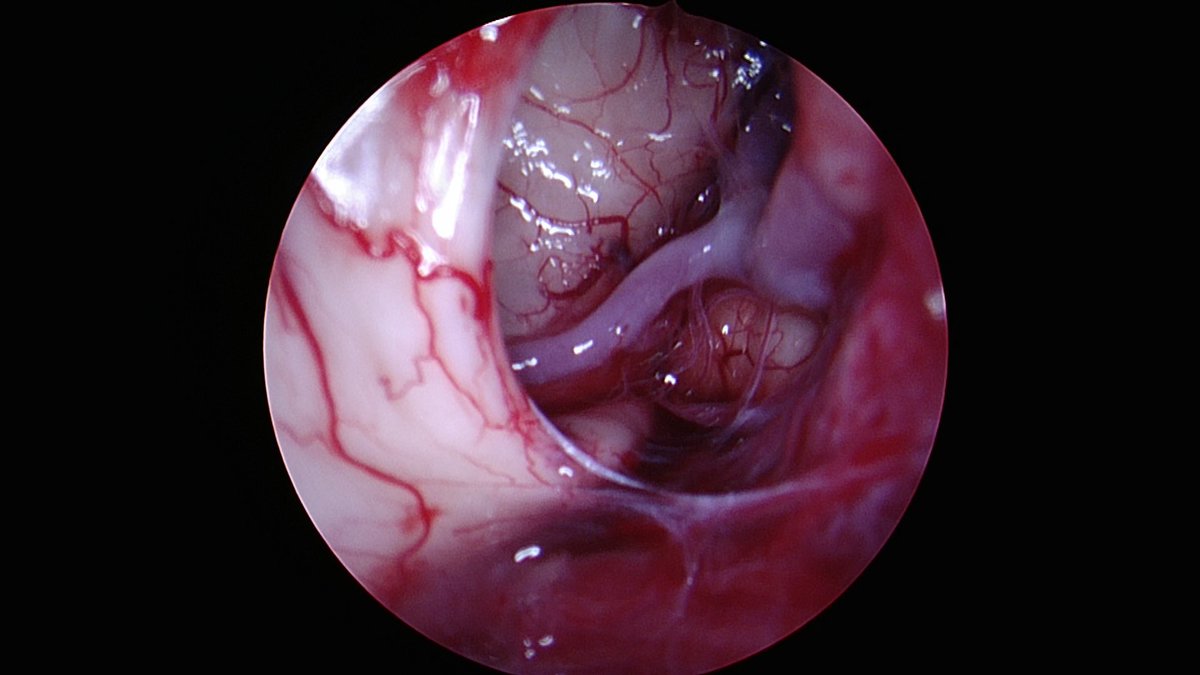

Symptomatic pontine #cavernous malformation causing 6th nerve palsy, gait disturbance and dysconjugate gaze. Left retrosigmoid transhorizental fissure approach and total resection with near complete resolution of pre-operative deficits at 6 weeks. CV Section